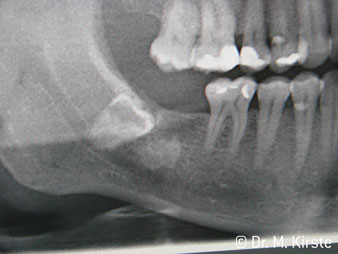

Die Winkelwahl des 45° Handstücks bringt viele Vorteile in der Anwendung. Chirurgisch tätige Kollegen, und für diese ist das Handstück in erster Linie entwickelt worden, werden schnell bemerken, dass man sehr gezielt arbeiten kann. Insbesondere bei der Weisheitszahnentfernung (Abb. 2) bedarf es keiner großen Weichteilabspreizungen im Wangenbereich (Abb. 3). Die Handstückkopfgestaltung kombiniert mit leichten Kopfdrehungen bei der Präparation lassen ein sicheres und schnelles Arbeiten im retromolaren Bereich zu.

Abb. 3